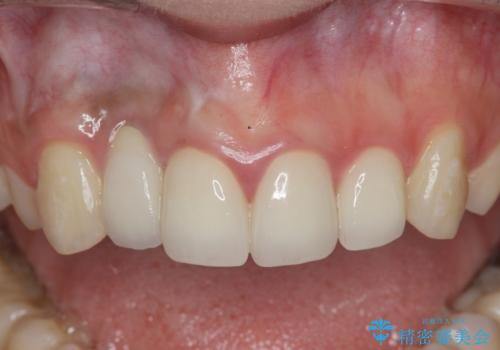

充填されたコンポジットレジン・再発した虫歯を神経に影響が出ないよう丁寧に除去し再充填をしたのちオールセラミッククラウンで前歯の審美性を回復します。

- 33万円(仮歯・ジルコニアクラウン×3)費用は治療当時の料金となります